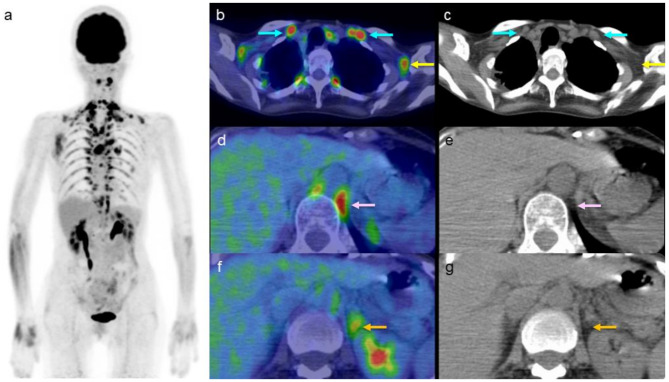

Background: Brown adipose tissues (BAT) are highly vascularized, mitochondria-rich tissues involved in thermogenesis. Physiological [18F]fluorodeoxyglucose ([18F]FDG) uptake in BAT can be influenced by several factors, including the use of medications that act on β-adrenergic receptors. Recently, increased [18F]FDG BAT uptake has been observed in elderly patients (≥ 60 years old) receiving β3-adrenergic receptor agonists. With the increasing use of β3-adrenergic receptor agonists for managing overactive bladder, there is limited understanding of their potential association with increased [18F]FDG BAT uptake. This study retrospectively investigated whether treatment with β3-adrenergic receptor agonists is associated with increased [18F]FDG BAT uptake among elderly patients. [18F]FDG positron emission tomography (PET) images were analyzed visually and through SUVmax measurements across eight predefined regions of interest (ROI): cervical, periclavicular, axillary, mediastinal, paravertebral, paraabdominal aortic, perirenal, and perisplenic regions. Patients' medication history and clinical records were reviewed to assess β3-adrenergic receptor agonist use relative to their [18F]FDG PET study.

Results: Forty-four elderly patients, each with a single [18F]FDG PET scan, were included in the analysis. Among the eight ROIs, the perirenal region showed a statistically significant increase in [18F]FDG BAT uptake in patients receiving β3-adrenergic receptor agonists compared with those not receiving, based on both visual analysis (p < 0.001) and SUVmax measurements (p = 0.030). All patients receiving β3-adrenergic receptor agonists demonstrated increased [18F]FDG BAT uptake in the paravertebral region.

Conclusion: In patients aged ≥ 60 years, β3-adrenergic receptor agonist therapy appears to be associated with increased [18F]FDG BAT uptake, particularly in the perirenal area.